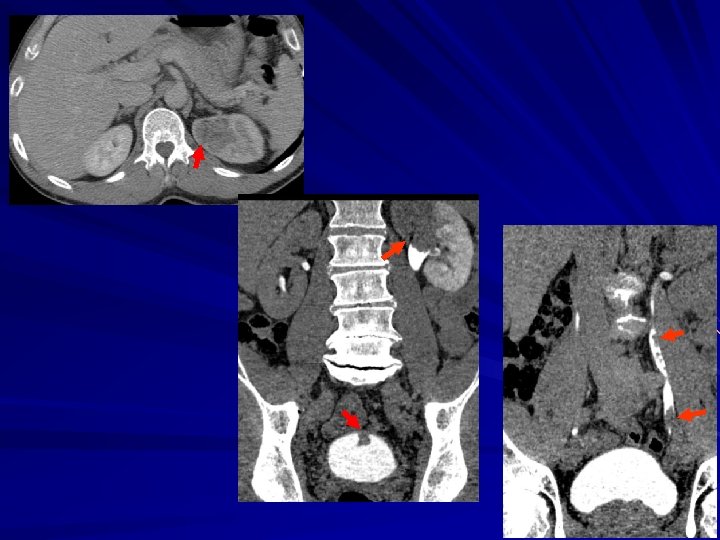

56 Y. O. man macrohematuria Rec. bladder TCC seen at cystoscopy Posterior view

Posterior view